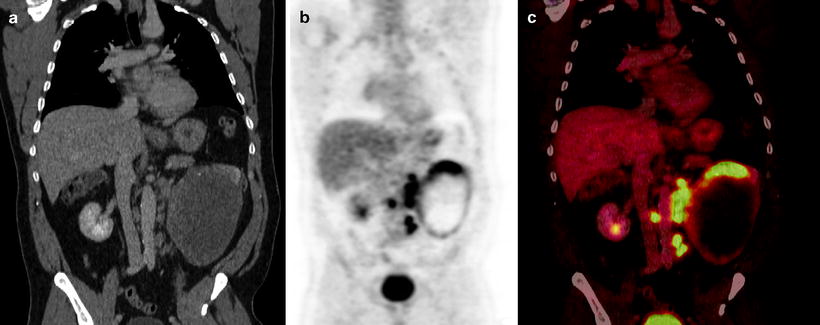

Dive into the stunning world of abstract Renal Cancer Pet/ct with vast arrays of imaginative images. highlighting the innovative use of photography, images, and pictures. ideal for modern art and design. Browse our premium Renal Cancer Pet/ct gallery featuring professionally curated photographs. Suitable for various applications including web design, social media, personal projects, and digital content creation All Renal Cancer Pet/ct images are available in high resolution with professional-grade quality, optimized for both digital and print applications, and include comprehensive metadata for easy organization and usage. Our Renal Cancer Pet/ct gallery offers diverse visual resources to bring your ideas to life. Time-saving browsing features help users locate ideal Renal Cancer Pet/ct images quickly. Reliable customer support ensures smooth experience throughout the Renal Cancer Pet/ct selection process. Cost-effective licensing makes professional Renal Cancer Pet/ct photography accessible to all budgets. Professional licensing options accommodate both commercial and educational usage requirements. Diverse style options within the Renal Cancer Pet/ct collection suit various aesthetic preferences. The Renal Cancer Pet/ct collection represents years of careful curation and professional standards. Each image in our Renal Cancer Pet/ct gallery undergoes rigorous quality assessment before inclusion. Multiple resolution options ensure optimal performance across different platforms and applications.